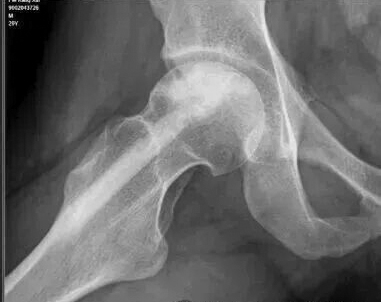

股骨头坏死的保头治疗,其核心在于清除坏死区域、重建血运并植入具有成骨潜能的活性材料。手术技术、材料选择以及对远期并发症的考量,共同决定着保头治疗的最终效果。本文分享一个采用富血小板血浆复合自体松质骨植骨的成功案例,并结合4年随访,探讨临床诊疗要点。 临床病例 患者为男性,25岁,因右侧髋部疼痛来到医院就诊。 术前影像学评估如下: X线检查:股骨头骨密度略有降低。 磁共振检查:右侧股骨头广泛骨髓水肿,提示病变处于进展期。此类影像学表现通常预示病情进展较快,单纯保守治疗或髓芯减压术难以阻挡塌陷的进程。 CT(计算机层析成像)检查:股骨头骨密度明显降低,骨小梁结构受损。这进一步印证了手术干预的必要性。 由于骨密度明显降低且硬化边界清晰,这名患者接受保守治疗或者髓芯减压术为时已晚。 手术方案与材料选择 考虑到这名患者年轻且坏死处于进展期,我和同事为他制定了复合植骨策略。 从髂嵴抽取骨髓,经分离提纯出自体干细胞与高浓度的富血小板血浆。 将高浓度营养因子(经分离提纯后的富血小板血浆富含多种生长因子)与自体松质骨混合,植入坏死区减压后的空腔。 将富血小板血浆制成凝胶,避免植入过程中发生流失。 术后随访与影像学演变 术后X线检查:植入骨填充良好,结构稳定。 术后1年X线检查:植入骨与宿主骨融合良好,遵循“该长则长,该消则消”的生理重塑原则,坏死区得到有效修复。 术后4年X线检查:修复区的骨小梁结构清晰,骨密度显著升高,甚至显示出比自体皮质骨更强的硬化性修复表现。这种力学强度的建立,使远期发生股骨头塌陷的风险极低。需要担心的是远期关节软骨的退变问题。 分析与体会 在对这名患者进行诊疗和随访的过程中,我们有以下体会: 关于死骨清除的边界 清除死骨并非多多益善。死骨与周围的硬化骨往往融为一体,边界难以精确判断。而硬化骨本身是重要的力学支撑结构,术中若伤及“无辜”,破坏了股骨头的原有支撑,反而得不偿失。 关于血运重建 鉴于股骨头内血供的复杂解剖,血运的改善更应侧重于疏通而非重建。通过髓芯减压术打通原有的血供通道,比试图建立一套全新的血运系统更现实、更可行。 关于远期关节软骨退变 这是保头治疗后需要直面的问题。即便骨性修复顺利完成、股骨头形态恢复良好,随着病程进展,缺血导致的关节软骨营养障碍仍可能逐渐显现。 术后4年,这名患者的关节面有裂开迹象,预示着软骨退变乃至骨性关节炎的进程难以完全逆转。 关于保头目标的再认识 保头治疗可延缓关节置换的时间,推迟骨性关节炎的进程。除日常生活中要控制体重、避免剧烈运动和重体力劳动外,对于已经出现关节炎症状的患者,可考虑采用关节腔内注射玻璃酸钠或自体富血小板血浆的方法,改善关节内环境、营养软骨。 关于手术时机 这名患者术前已处于进展期。 临床上,多数患者往往在股骨头即将塌陷时才接受植骨治疗,这在一定程度上决定了保头治疗效果的“有效期”。理想状态下,对于ARCO(国际骨循环研究协会)ⅡB期及更早期的患者,保头治疗成功后有望获得10年乃至更长无关节炎症状的生存期。然而,临床中普遍存在一种现象:不到病变部位即将塌陷,患者往往难以接受尽早进行植骨修复。 总之,富血小板血浆复合自体松质骨植骨为进展期股骨头坏死患者提供了一种更有效的修复策略,能减少骨吸收、缩短骨性愈合时间,从而获得足够的力学支撑。术后需将关节软骨退变纳入长期随访管理范畴,并基于患者的病情、年龄及功能需求开展预期管理,引导患者建立符合自身实际的康复目标与疾病认知。 (作者供职于河南省洛阳正骨医院)